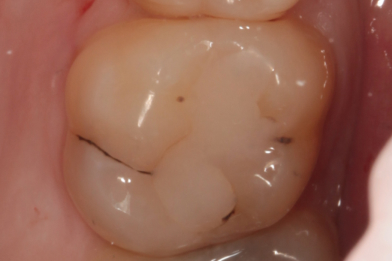

Пациент обратился с жалобами на боли во время приема пищи. После обследования была выявлена устаревшая пломба с дефектом на жевательном

Бояринов Сергей Эдуардович

зубе. Произведено лечение: снятие старой пломбы с последующим восстановлением анатомо-физиологический формы при помощи пломбировочного материала. -